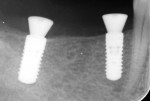

A 65-year-old woman with no contributory medical history was referred by her general dentist for the restoration of the mandibular right quadrant with an implant-supported fixed restoration. Using 3D planning and a surgical guide, implants Nos. 29 and 31 were placed. After a healing period of 8 weeks, as recommended by the manufacturer, the two implants were ready for restoration (Figure 1 and Figure 2).